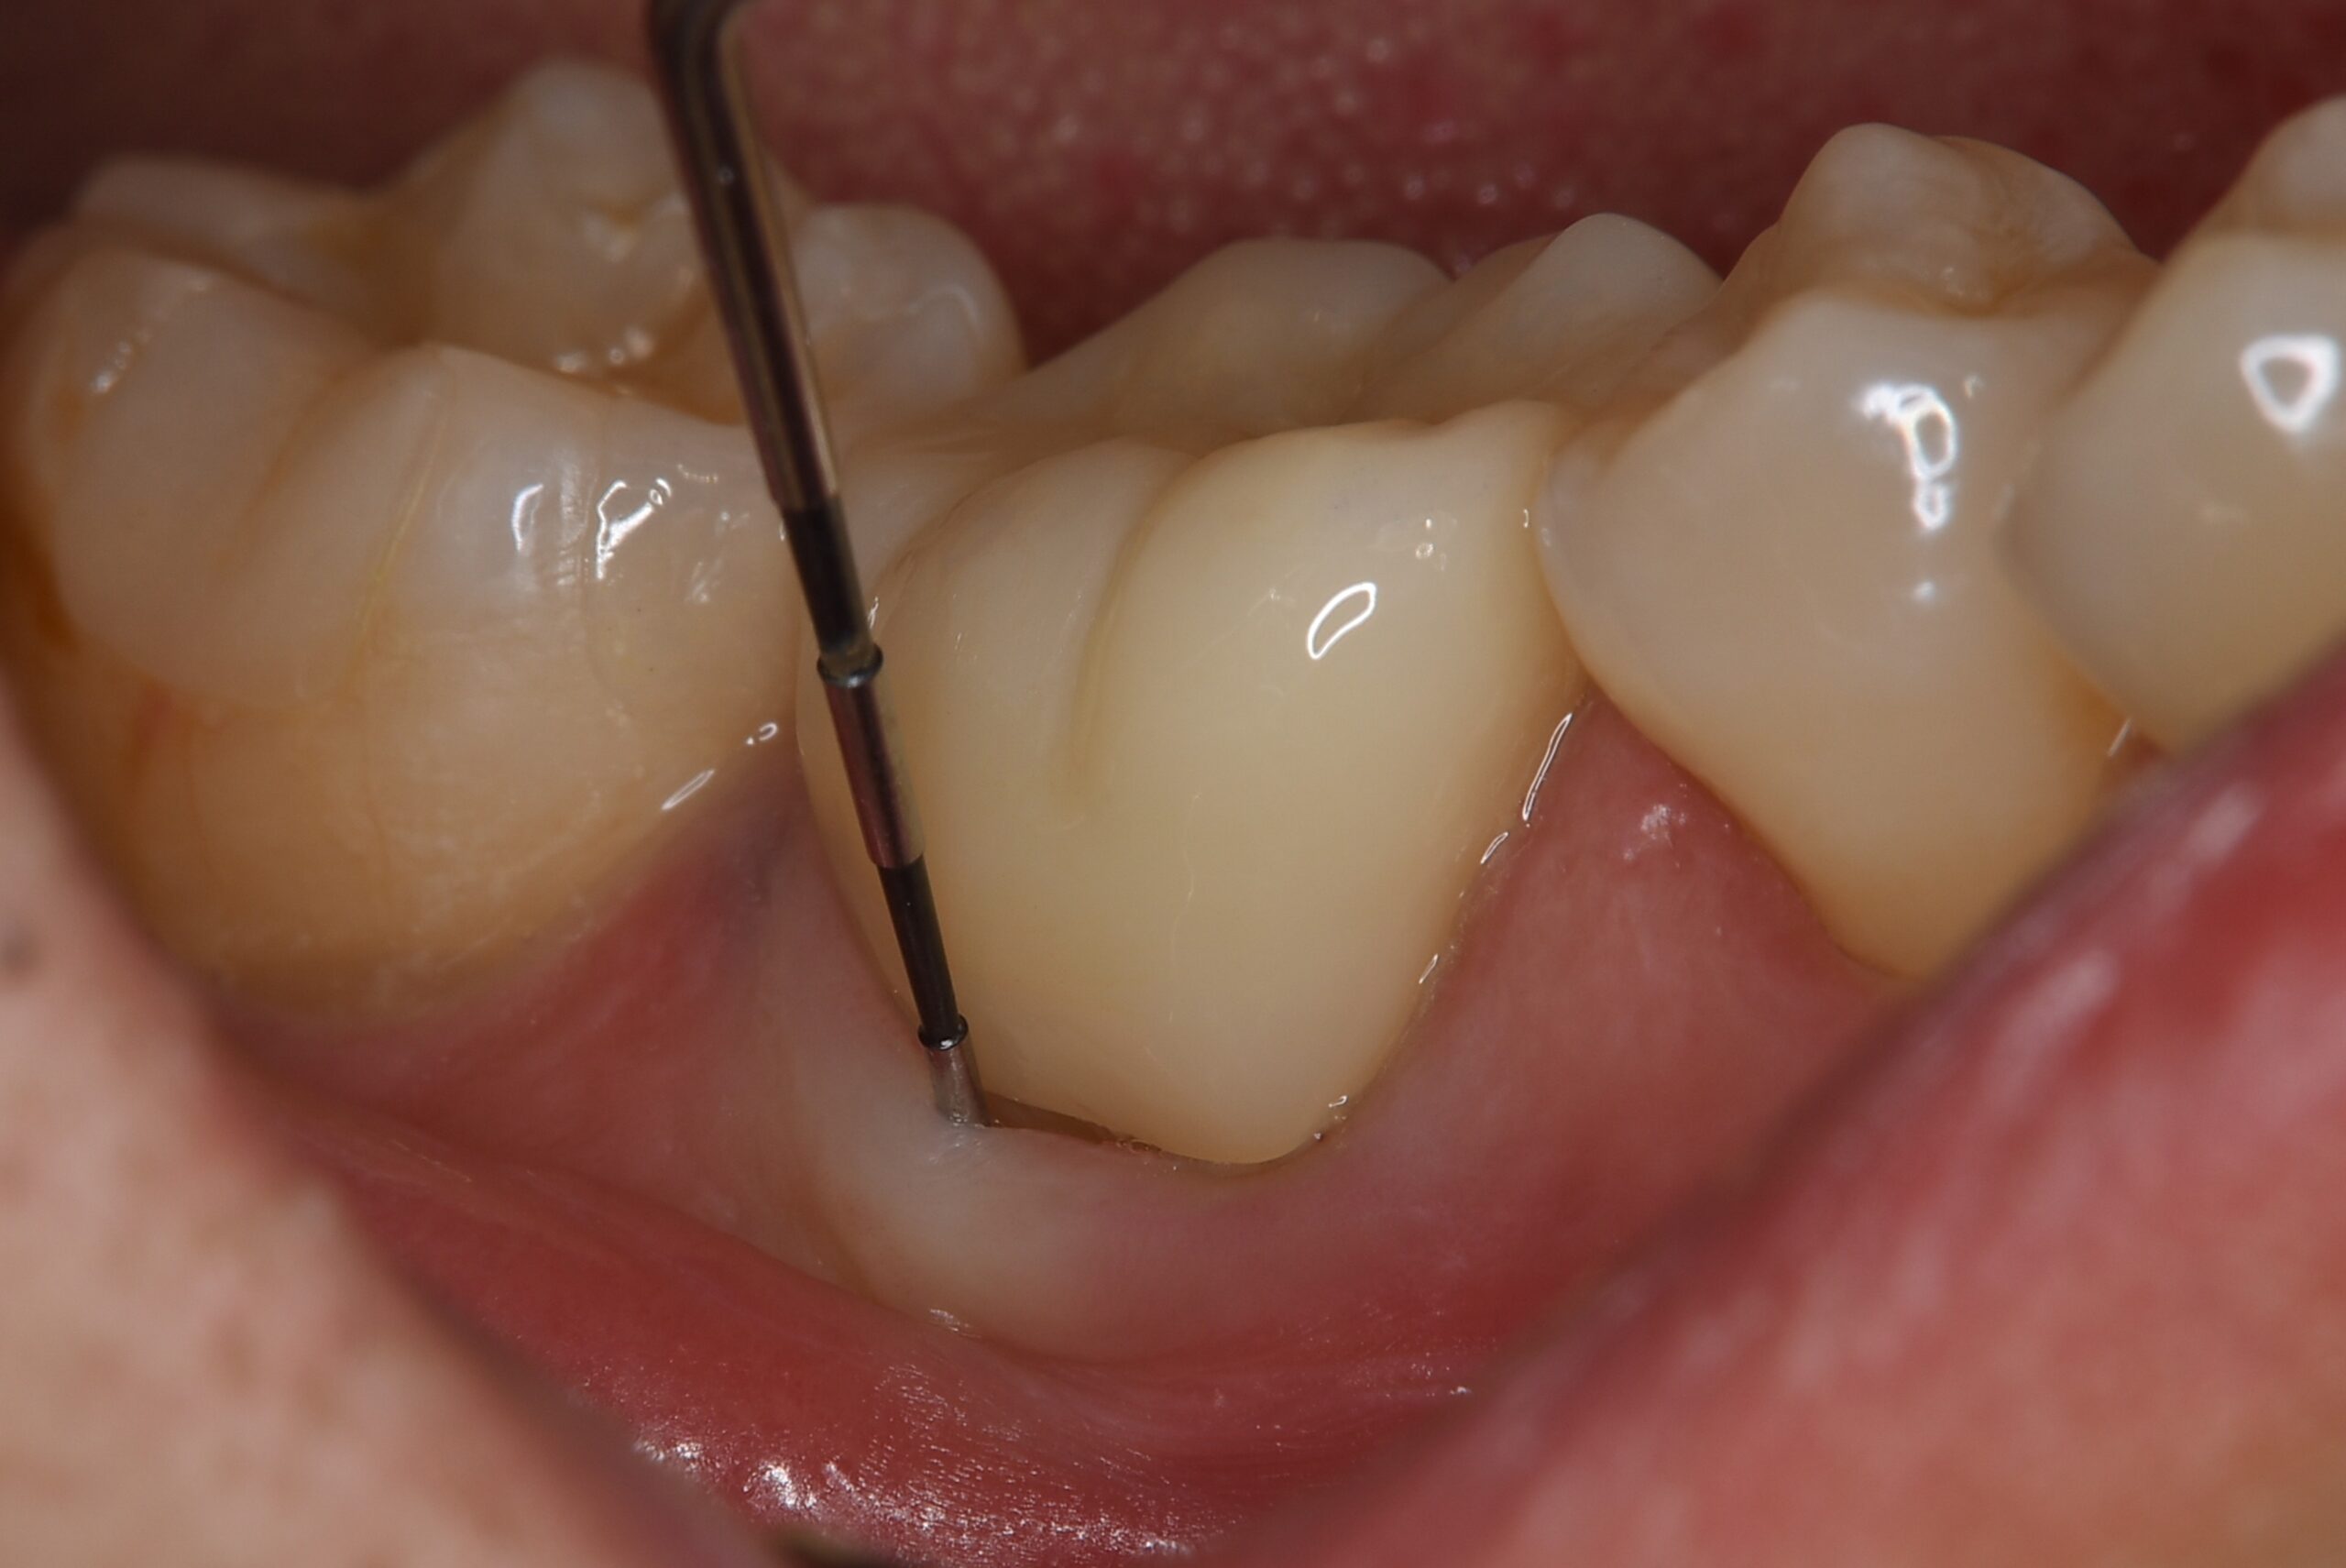

症例6

| 患者様データ | 50代 女性 |

| 来院時の主訴 | 「歯茎から出血する。口の中が全体的に痛い。」 |

| 医院の診断 | 虫歯の再発、重度の歯周病を併発した慢性根尖性歯周炎 |

一般的に歯周病と根尖病変の混合病変は非常にシビアな状態と言われています。この患者様の場合、根管治療と歯周病の再生療法を併用することにより、健全な状態に改善することができました。 |